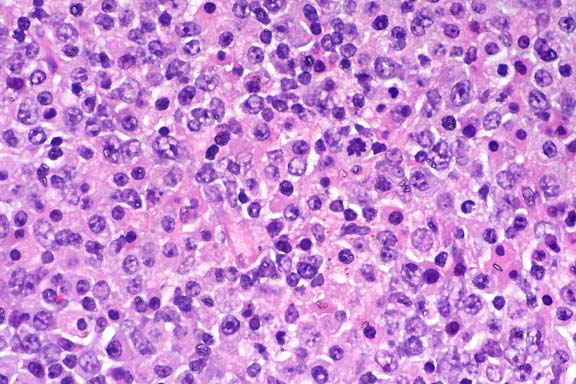

The specimen consists of skin and subjacent thigh muscle. Focal ulceration with severe neutrophilic inflammation is present in the epidermis. There is widespread suppurative inflammation, granulation tissue and coagulation necrosis in the muscle. Individual myofibers are swollen, hyalinized, and fragmented. Marked numbers of neutrophils surround myofibers undergoing myocytolysis and mineralization.

With intramuscular injection, gross lesions vary depending on the dose administered and the numbers of days post-injection. In rats and hamsters at one day post-injection (DPI), subcutaneous and fascial hemorrhage, edema, and brownish discoloration of the tissue are found. At 3 DPI, pale white areas in the muscle with ulcers over the injection site are observed. Lesions become more severe with higher doses. Histologically, there is a central area of muscle necrosis characterized by sarcoplasmic swelling, hyalinization of muscle fibers, loss of striations, fragmentation, and centralized or faded nuclei. At 24 hours post-injection, a zone of inflammatory cells composed primarily of neutrophils surrounds necrotic muscle, while at three to seven days, lymphocytes, macrophages, and fibroblasts predominate. At 14 DPI, fibrous connective tissue and small foci of mineralization replace large bands of muscle.